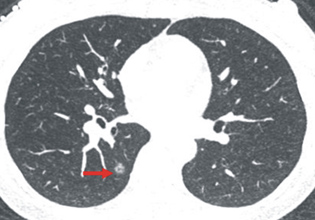

李小姐的低劑量胸部電腦斷層影像發現肺部右

下肺陰影(紅色箭頭所指)